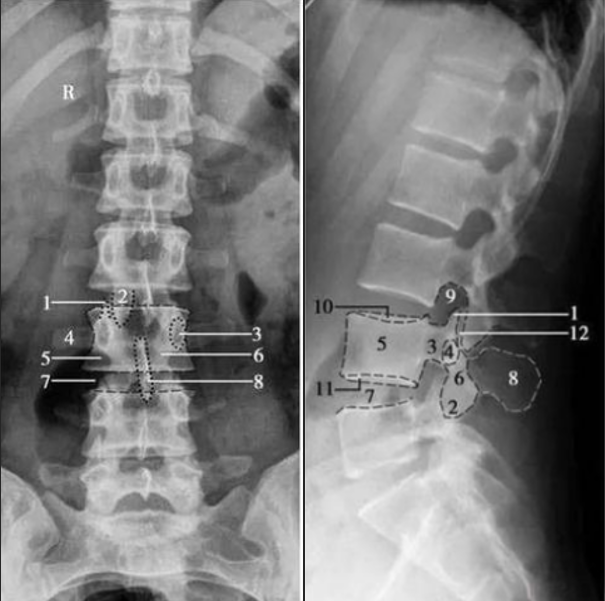

腰椎正側(cè)位

1. 上關(guān)節(jié)突;2. 下關(guān)節(jié)突;3. 椎弓根;4. 橫突;5. 椎體;6. 椎弓板;7. 椎間隙;8. 棘突;9. 椎間孔;10. 椎體上終板;11. 椎體下終板;12. 椎突間關(guān)節(jié)

腰椎正位片主要體現(xiàn)腰椎整體的力線、骨骼結(jié)構(gòu)及對(duì)稱性,是腰椎X線篩查病變的基礎(chǔ)體位。

腰椎側(cè)位片是評(píng)價(jià)腰椎生理曲度、椎間盤高度以及椎體穩(wěn)定性的重要依據(jù)。